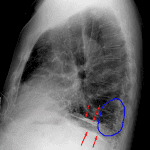

Age: 83

Sex: Male

Indication: Pre-op

Sample ReportBilateral pleural plaques and interstitial coarsening, most prominent at the lung bases. Findings are most suggestive of asbestosis. Consider chest CT for further evaluation.

No definite superimposed focal airspace disease.

Mild cardiomegaly.